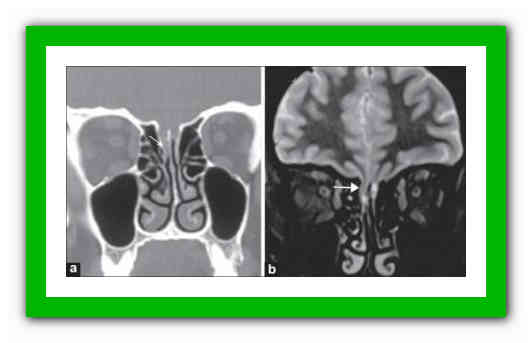

- Компьютерная томография (КТ) основания черепа и околоносовых пазух (на рисунке определяется большой дефект основания черепа в проекции ситовидной пластинки с формированием менингоцеле (показано стрелкой)).

- Магнитно-резонансная томография (МРТ) – дополнение к КТ для исключения менингоэнцефалоцеле.